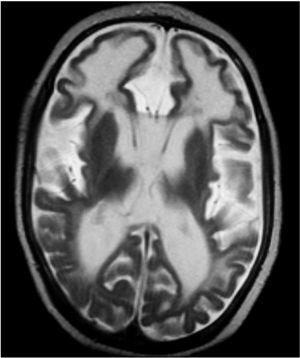

Entre las exploraciones complementarias realizadas destacan: transaminasemia, amoniemia, ácido láctico y pirúvico plasmático, aminoácidos en sangre y orina, ácidos orgánicos en orina, estudio citoquímico convencional de LCR, serologías TORCH, cariotipo, PEAT, EEG y fondo de ojo, normales; PEV desestructurados. La RM cerebral realizada a los 11 meses de edad mostraba lesiones quísticas periventriculares, signos de atrofia cortical y aumento de la señal en la sustancia blanca periventricular. La TC craneal realizada a los 24 meses de edad revelaba calcificaciones bilaterales en los núcleos de la base y alguna periventricular, con disminución global del grosor de la sustancia blanca. El IFN-α en LCR y sangre mostró valores elevados (4 y 25 U/ml, respectivamente).